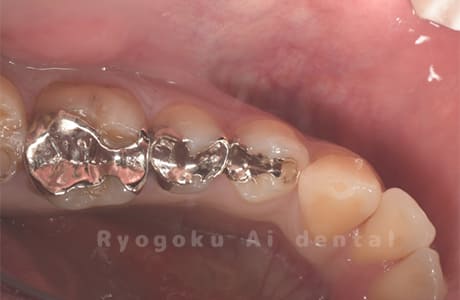

Case11

-

- 原因

- インレー2次カリエス、ならびにインレー脱離

- 治療内容

- セラミッククラウン、セラミックインレー

- 治療費用

- 123,000円×2(セラミッククラン)、77,000円(セラミックインレー)

銀歯が取れて、ご来院された患者様です。奥歯2本をセラミッククラウン、手前の小臼歯をセラミックインレーで治療を行いました。

<リスク・副作用>

過度の咬合や衝撃で割れることがあります。